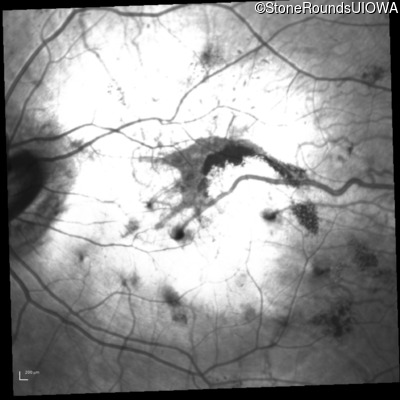

Fundus Photography - Right - 5/300

Exemplar

Fundus Montage - Right - 5/300